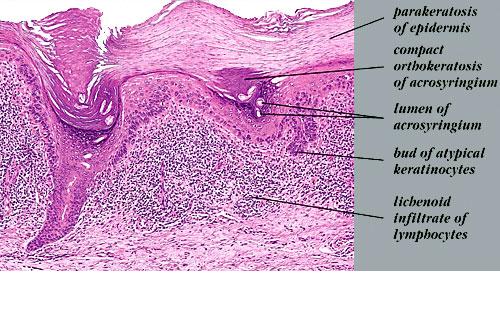

Read MoreSolar keratosis with lichenoid infiltrate of lymphocytes = التقران الضيائي مع ارتشاح حزازاني للخلايا اللمفاوية